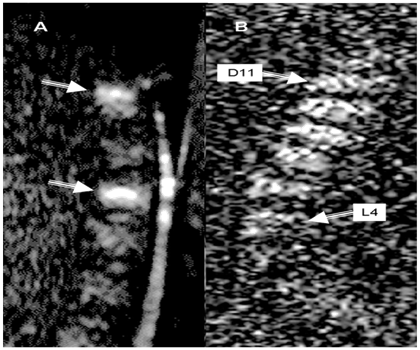

Vertebral fracture in an older person, particularly one with a history of cancer, is due to OP or is the result of a metastasis, is a not infrequent clinical problem that has important prognostic and therapeutic implications. The two types of fracture are usually indistinguishable on plain radiographs and require higher order imaging for diagnosis. Complete replacement of the normal bone marrow and a convex posterior contour of the vertebral body, favors a fracture of neoplastic origin. Using diffusion-weighted imaging and/or chemical shift imaging may be helpful in difficult cases.7,19 Diffusion-weighted sequences have been proposed as a helpful adjunct in the differentiation of acute benign osteoporotic fractures from pathologic fractures of the spine.20 Diffusion-weighted sequences are sensitive to molecular motion because random motion of water molecules in gradient fields produces phase dispersion and therefore, signal attenuation. Water in vital tumor cells shows lower mobility as a result of cellular structures.21 In the presence of diffusion-sensitizing gradients, this finding should result in a lower signal attenuation compared with stronger dephasing of more mobile extracellular water with extensive signal attenuation. Accordingly, diffusion weighted imaging could differentiate benign (osteoporotic and traumatic) and malignant vertebral fractures.22 Hypo- or isointense signal intensity in an acute vertebral wedge fracture indicates a benign osteoporotic fracture [Figure 5], whereas hyperintensity indicates a metastatic fracture [Figure 6]. Hypo- or isointense signal was diagnostic for an acute benign fracture, whereas high signal intensity was suggestive of pathologic bone marrow replacement. The low signal intensity of acute benign vertebral compression fractures on diffusion-weighted images may be due to bone marrow edema, leading to an increase in the mean free path length of water protons and therefore to a signal loss in the fractured areas. Moreover increasing diffusion weighting can reduce false-positive hyperintense osteoporotic fractures or make hypointensity more obvious in cases of osteoporotic fractures. It is noteworthy to mention that if the findings on routine T1-weighted SE and STIR images are not completely conclusive for a diagnosis of acute benign or pathologic vertebral compression fracture, then diffusion-weighted imaging of the spine is indicated.23

Figure 6 Metastatic breast cancer.

Figure 6B multiple myeloma (D11-L4), Sagital diffusion weighted images (DWIs) both lesions showed evidence of diffusion restriction indicated by white arrows.